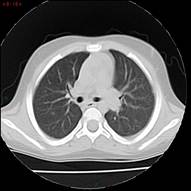

Al mes de haber suspendido tratamiento, presenta RAE: 5.220/mm3 por lo que reinicia meprednisona 1 mg/kg/día vía oral. Con laboratorio control a los 11 días y RAE en descenso se decide descender glucocorticoide para evitar efectos adversos a largo plazo hasta suspenderlo y asociar hidroxiurea a 15 mg/kg/día vía oral como ahorrador de glucocorticoide. Se cita al paciente cada 10 días para evaluar curva de descenso de RAE. En los controles posteriores el paciente comienza a desmejorar, presentando anemia con requerimiento transfusional, RAE: 5.600/mm3, ERS y PCR en ascenso, agrega síndrome febril intermitente y compromiso respiratorio. Se diagnostica neumonía unifocal izquierda. Se realizaron hemocultivos, que fueron negativos, y aspirado para gérmenes comunes y COVID. que fue negativo. Se realiza TAC de tórax donde se observa imagen compatible con neumopatía infiltrativa. Se realiza lavado broncoalveolar, observándose infiltrado eosinofílico 60% con cultivo negativo para Aspergilosis asociada a eosinofilia en contexto de tratamiento inmunosupresor.

En marzo 2024, al presentar Gb: 17.000/mm3, RAE: 7.180/mm3 en monoterapia con hidroxiurea a dosis plena se decide suspender medicación para reevaluación de daño. La evaluación cardiológica es normal, mientras que la evaluación pulmonar tomográfica muestra un nuevo nódulo pulmonar en segmento basal de lóbulo superior intraparenquimatoso y una imagen inferior de 4 mm no biopsiable. Se realiza BAL, sin eosinofilia.